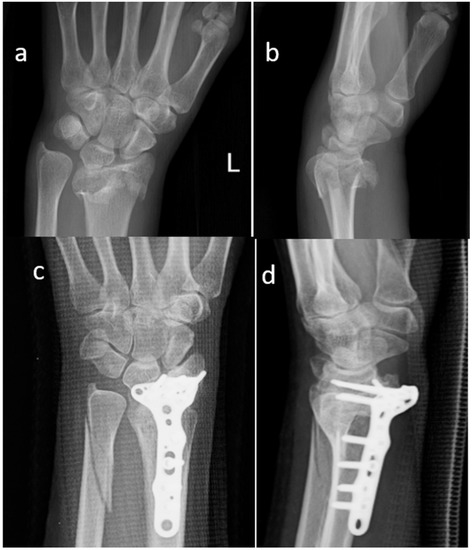

Figure 1.

Standard X-ray of a displaced articular fracture of the distal radius associated with multifragmented distal ulnar fracture. Preoperative images in AP (a) and Lateral (b) view are compared to post-operative X Ray at 2 months (c,d). The osteosynthesis appears stable and the xenograft block appears stable. (Female, 34 yy).